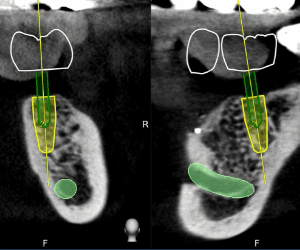

全球動態醫療導航最高精準度0.2mm,最先進的時時導航技術,可以手術當下即時反映出植牙鑽針的角度、深度、位置等資訊,精準定位植體位置。

導航技術讓醫師能夠及時掌握植體在牙脊中的深度與角度,避免傷害到鼻竇腔與神經管,同時手術開刀範圍縮小,達到真正的微創植牙,相對也大幅降低術後的疼痛與腫脹感。

最新牙科導航儀,只需讓病患拍攝一次的斷層掃描,避免過量的輻射劑量,同時輔助牙醫師在植體定位更精準,取代傳統醫師僅憑手感植牙,降低手術風險,提高診療效率。

鼻竇腔位置

貫穿鼻竇很有可能導致鼻竇炎、頰部疼痛、眩暈後遺症,或是植牙失敗

神經管位置

植入植體時如果不小心切到了神經,除了傷及神經,還可能導致臉部麻痺。